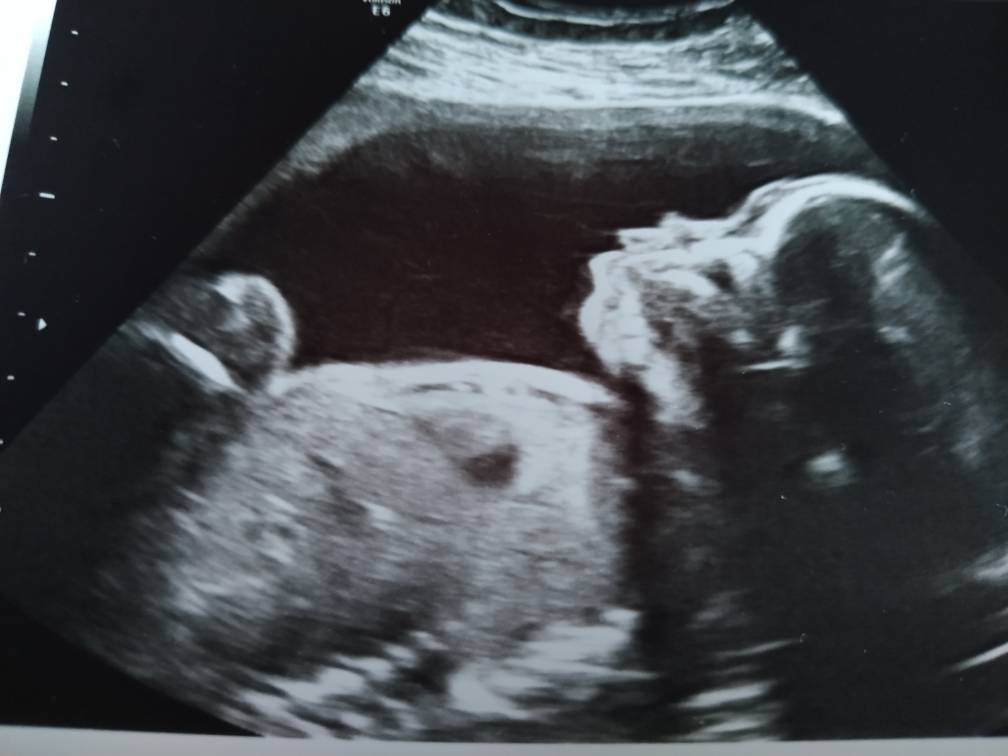

Bylam dzisiaj na USG a to moja kochana córeczka [emoji3590] Anastazja [emoji7][emoji7]

Bylam dzisiaj na USG a to moja kochana córeczka [emoji3590] Anastazja [emoji7][emoji7]Zobacz załącznik 996712

Jej jaka śliczna <3 pulorki już ma fajne :)